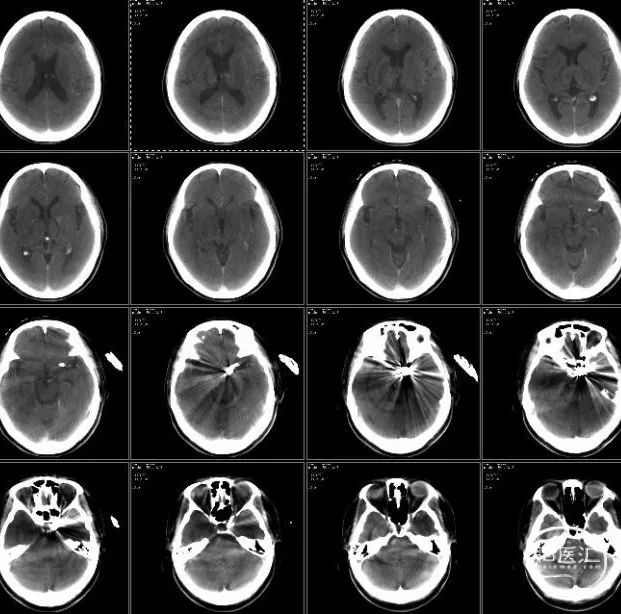

术前影像检查

双侧椎动脉造影。

右侧颈总动脉造影,右侧脉络前动脉小动脉瘤,形态规则,大小约2mm。

左侧颈总动脉造影示左侧颈内动脉后交通段动脉瘤,大小9.22*10.18mm,颈宽约8.74,远近端载瘤动脉直径分别为3.47、4.0mm;左侧脉络膜动脉微小动脉瘤,大小约1mm。

脑部平扫可见左侧额顶叶点状亚急性梗死灶HRMRI。

MRA及薄层T2可见左侧颈内动脉后交通段瘤样突起。

T1 SPACE可见左侧颈内动脉后交通段动脉瘤,瘤壁稍强化。